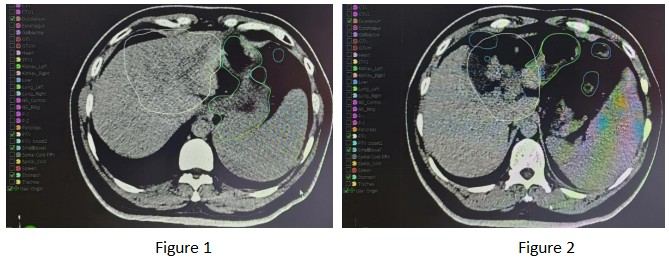

Based on the above imaging examinations, the patient currently has no evidence of distant metastasis, and carbon ion therapy can be performed. On March 4, 2025, the patient underwent radical carbon ion therapy for malignant hepatic tumors. The patient was treated in the prone position. The GTV was delineated based on the hepatic lesions visible on the positioning CT, abdominal MRI, and PET-CT; the ITV was delineated based on the hepatic lesions in all respiratory phases combined with 4D-CT; the GTVm was delineated based on the portal vein tumor thrombus visible on the positioning CT, abdominal MRI, and PET-CT; the CTV was GTV + GTVm + 5 mm, and the CTV was expanded by 5 mm to form the PTV; the PTVboost1 was the PTV avoiding the stomach, small intestine, and duodenum by 8 mm (as shown in Figures 1 and 2).

Prescription dose: PTV: 40 Gy (RBE)/9 fractions; PTVboost1: 8 Gy (RBE)/2 fractions (as shown in Figure 3).